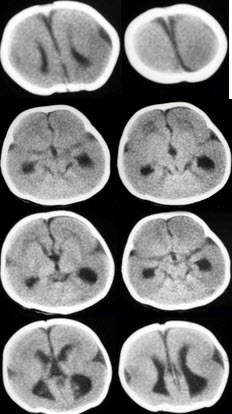

男,35岁,间歇性癫痫发作20余年,CT检查如图,最可能的诊断为( )

A:表皮样囊肿

B:血管母细胞瘤

C:胼胝体发育不良

D:灰质异位

E:脑囊肿